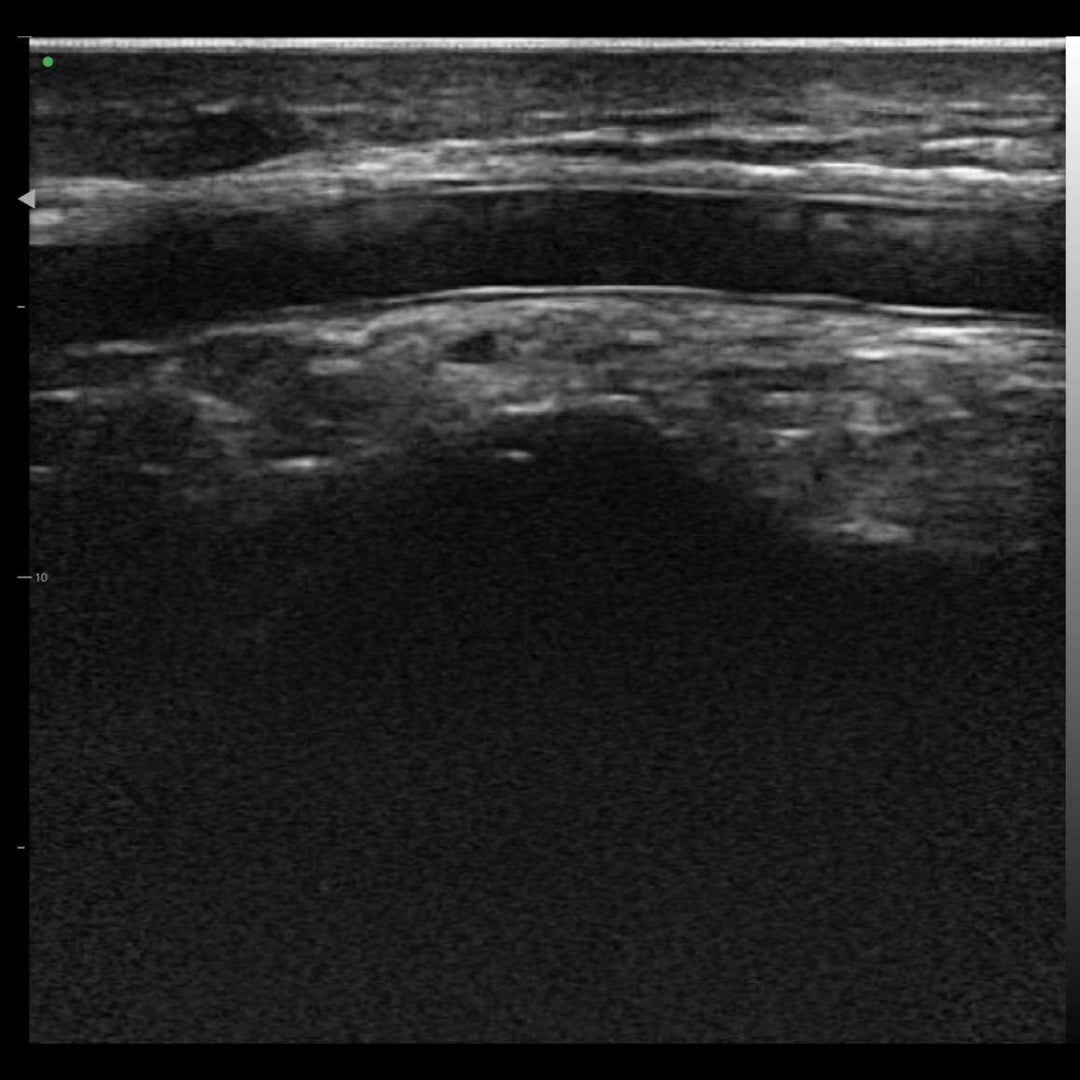

Diseñado con una plataforma innovadora de integración y procesamiento de datos, nuestro Transductor Lineal de Ultra Alta Definición HM20L visualiza claramente en tiempo real los vasos faciales, nervios, capas cutáneas y subcutáneas de las redes neurovasculares faciales para guiar de manera segura los procedimientos. Esto elimina riesgos y garantiza la seguridad de los pacientes.

Imágenes de la vida real

Nuestros dispositivos reproducen una excelente calidad de imagen.